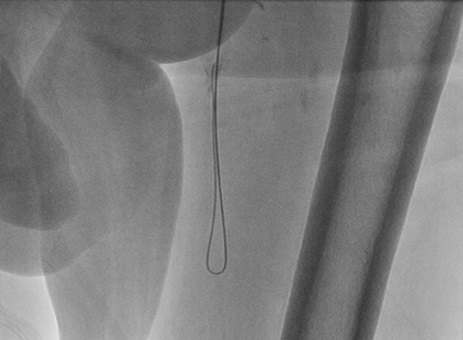

A 70-year-old gentleman with an extensive history of tobacco abuse and a non-ischemic cardiomyopathy presents with left leg claudication for the last 8 years.  His resting ABIs are right 1.00, left .80.  A 6F Ansel (Cook Medical) was selectively engaged into the common femoral artery and in spite of the fact that it was difficult to delineate the origin of the SFA, we passed the .014 Command wire (Abbott Vascular, Abbott Park, Illinois) with the CrossLock™ balloon catheter.  The FrontRunner™ was passed through the Rx port of the CrossLock™ and with the wire pulled back and the CrossLock™ balloon inflated, we were able to pass the FrontRunner™ across the total occlusion.  This was followed by balloon angioplasty and then multiple drug eluting balloons (Lutonix, Bard Peripheral, Tempe, Arizona).  Following this, there was excellent patency and runoff.

Figure 14. Final angiogram showing 3 vessel runoffs.